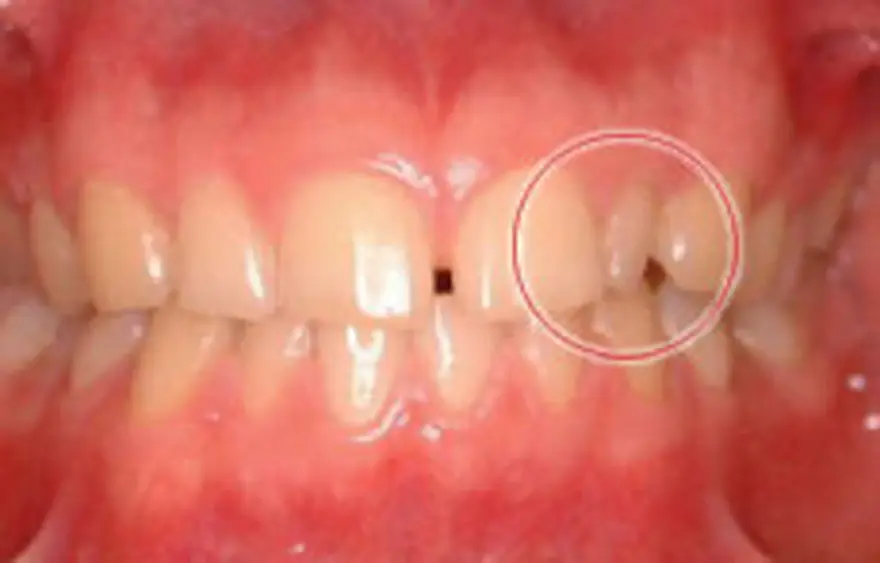

MTM(部分的な矯正)治療例2

矮小歯にセラミックを被せたケース

| 患者さまの年齢・性別 | 30代・女性 |

|---|---|

| 治療期間 | 5ヵ月 |

| 治療費(税込) | 242,000円 |

| 主訴 | 前歯の隙間が気になる。 |

| 診断名・主な症状 | 正中離開 左上の前歯の横の歯が矮小歯という本来より小さい歯です。 |

| 治療に用いた主な装置 | セルフライゲーションブラケット装置(デイモンシステム) |

| 治療内容 | 中央の隙間を閉じた後、そのままでは再度隙間があいてしまうおそれがあります。そのため、矮小歯の表面をわずかに削り、セラミックのシェルを表面につけて歯の幅を広くしています。 |

| 抜歯部位 | 非抜歯 |

| 通院回数・メンテナンス頻度 | 5回 |